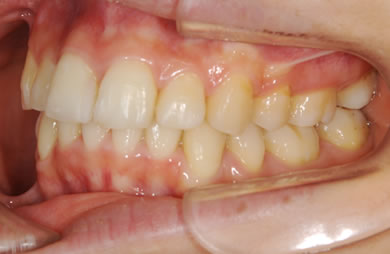

全顎矯正治療+セラミック治療

| 性別/年齢 | 女性 / 26歳 | ||||||||||||||||||||||||||||||||

| 主訴 | 上下乱ぐい歯と出っ歯を治したい。 | ||||||||||||||||||||||||||||||||

| 治療方針 | 口元が出ていていること、がたつきが大きいことより、上下左右の第一小臼歯および親知らずを抜歯し、マルチブラケット治療を行う。抜歯した隙間を活用できるよう上顎にはインプラントアンカー(釘)を使用し、その釘より歯を後ろに移動する。 | ||||||||||||||||||||||||||||||||

| 治療内容 | 唇側矯正(シルバー)、矯正用スピードインプラント、ハイブリッドセラミックインレー2本 | ||||||||||||||||||||||||||||||||

| 総治療費 | 802,700円 | ||||||||||||||||||||||||||||||||

| 治療期間 | 2年3ヶ月 |